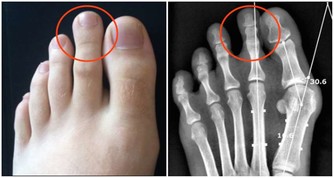

三、大便變細

如果腸道裡面出現了腫瘤細胞,這些腫瘤細胞就會快速的繁殖,導致腸道的空間變窄,大便也因此會變細,尤其是直腸部位出現腫瘤細胞之後這種情況更加明顯。

所以,一旦發現自己的大便變得越來越細就要及時到醫院檢查治療,以免腸道完全阻塞之後無法順利排便。癌症進入晚期之後會大大的增加治療的難度,使生命受到嚴重的威脅。